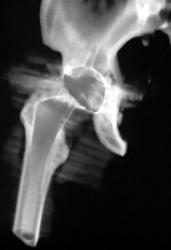

Transverse Process Fracture With Hematoma